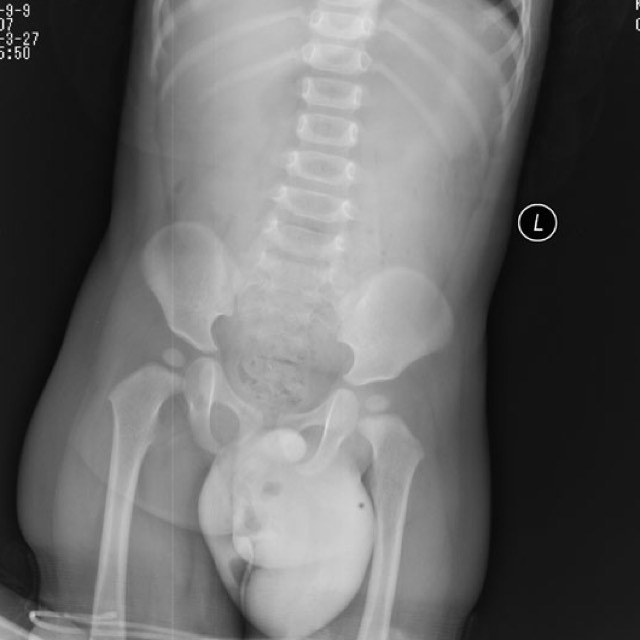

1岁男婴,发现腹股沟可复性包块半年。平片:左盆腔下方可见团状软组织块影,其内可见散在气体影,结合临床考虑为腹股沟疝。